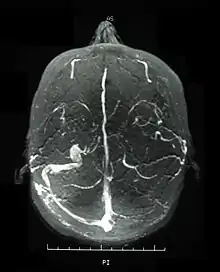

Magnetic resonance venogram demonstrating occlusion of the left sigmoid and transverse sinuses

Visual acuity, or color vision loss with concurrent mucocutaneous lesions or systemic Behçet's disease symptoms should raise suspicion of optic nerve involvement in Behçet's disease and prompt a work-up for Behçet's disease if not previously diagnosed in addition to an ocular work-up. Diagnosis of Behçet's disease is based on clinical findings including oral and genital ulcers, skin lesions such as erythema nodosum, acne, or folliculitis, ocular inflammatory findings and a pathergy reaction. Inflammatory markers such ESR, and CRP may be elevated. A complete ophthalmic examination may include a slit lamp examination, optical coherence tomography to detect nerve loss, visual field examinations, fundoscopic examination to assess optic disc atrophy and retinal disease, fundoscopic angiography, and visual evoked potentials, which may demonstrate increased latency. Optic nerve enhancement may be identified on Magnetic Resonance Imaging (MRI) in some patients with acute optic neuropathy. However, a normal study does not rule out optic neuropathy. Cerebrospinal fluid (CSF) analysis may demonstrate elevated protein level with or without pleocytosis. Imaging including angiography may be indicated to identify dural venous sinus thrombosis as a cause of intracranial hypertension and optic atrophy.